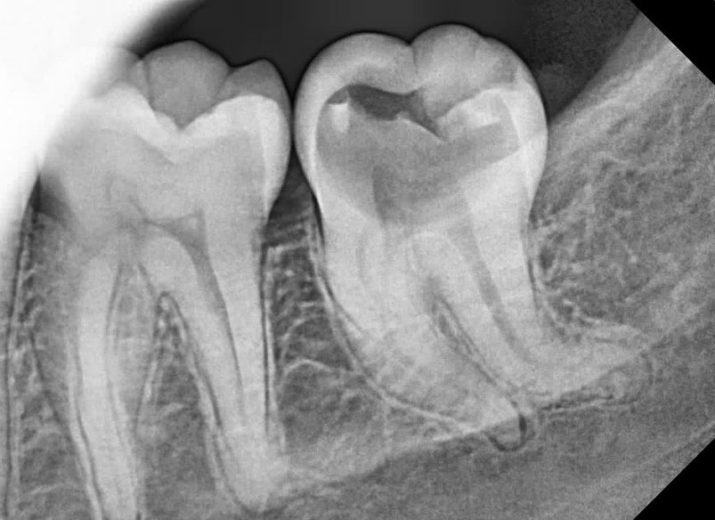

کانال‌های کِرو دار

Severe curve:mandibular second molar.